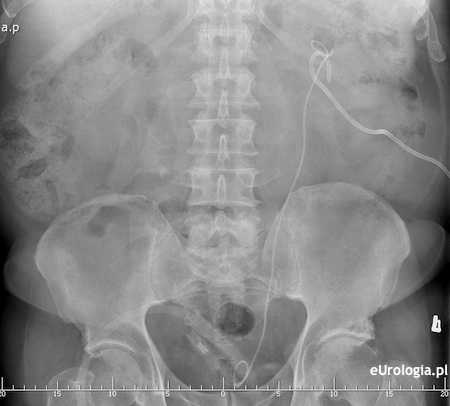

Fot. Zdjęcie przeglądowe jamy brzusznej pacjenta z założonym cewnikiem DJ i nefrostomią.

W codziennej praktyce czasami dochodzi do sytuacji, że pacjent ma założone równocześnie dwa rodzaje drenażu. Założenie nefrostomii u pacjenta z cewnikiem DJ w moczowodzie konieczne jest w sytuacji gdy drenaż cewnikiem DJ jest niewystarczający. Po uzyskaniu niskociśnieniowego odpływu moczu z reguły rezygnuje się z jednego rodzaju drenażu. Nie wiemy jaka jest przyczyna wodonercza obustronnego u Pani matki. Warto w takim przypadku porozmawiać z urologiem na temat ewentualnego usunięcia któregoś z cewników. Nie znając stanu klinicznego pacjentki i obrazu badań obrazowych trudno wypowiadać się na temat usunięcia któregoś z cewników...